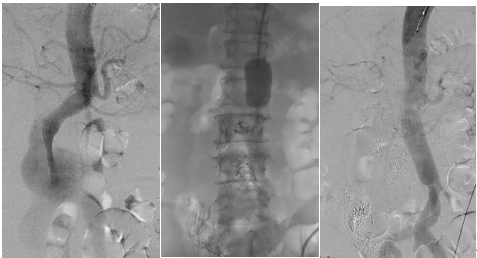

患者術前造影,動脈瘤最大直徑達6.9厘米(左);術者用主動脈大球囊阻斷腹主動脈(中);血管置換術后造影,血流恢復正常(右)